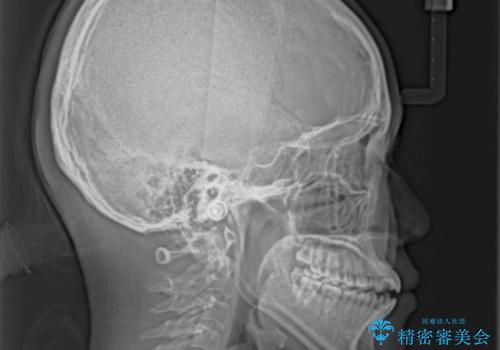

- 上下前歯の隙間と咬み合わない前歯を気にして来院された患者様です。

開咬の治療は、前歯を閉じるように動かすとともに、上下臼歯を圧下(骨内にめり込ませる)させることで進めて行きます。

インビザラインは臼歯の圧下を効果的に行えるため、インビザラインを用いて矯正治療を行うこととしました。